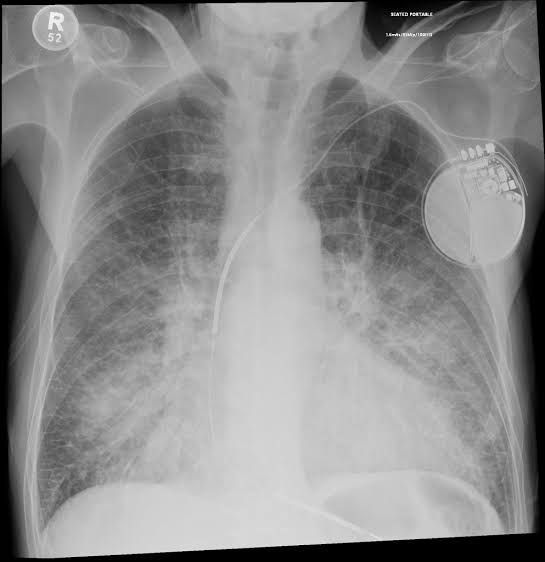

Pulmonary congestion is defined as accumulation of fluid in the lungs, resulting in impaired gas exchange and arterial hypoxemia. It occurs sequentially, first developing in the hilar region of the lungs, followed by filling of the interstitial space and finally, in its most severe form, by alveolar flooding.